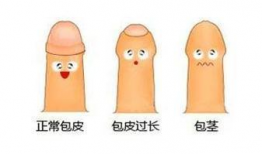

包皮手术 视频,专业视频带你了解手术细节

最近是不是有很多小伙伴在为“包皮手术”这个话题纠结呢?别急,今天我就来给你详细聊聊这个话题,让你对它有个全面的认识。而且,我还准...

2025-11-22 132 -